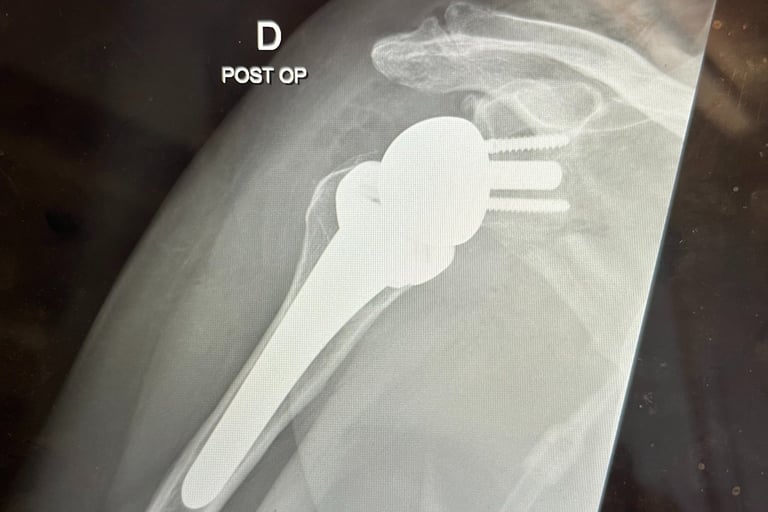

Spalla

Mi occupo del trattamento delle principali patologie della spalla, con particolare esperienza nella protesica di spalla (anatomica e inversa). Tratto inoltre instabilità di spalla, lesioni della cuffia dei rotatori e traumatologia della spalla, con l’obiettivo di ripristinare la funzione articolare e ridurre il dolore attraverso tecniche chirurgiche moderne e personalizzate.